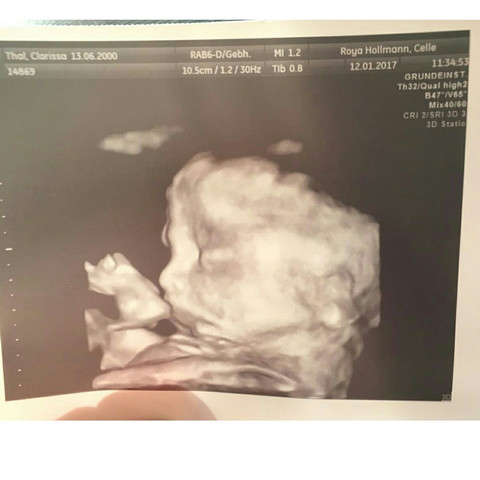

Dies sind Neugeborene, die vor 37 vollendeten Schwangerschaftswochen (SSW) zur Welt kommen Rund 8000 dieser Kinder sind sehr kleine Frühgeborene unter 30 SSW, und ca 1000 sind extremst kleine Frühgeborene von 24 und 25 SSW, die große Anforderungen an die Neugeborenenmedizin stellen. Als wir in der 25SSW waren, haben wir ein 3DUlltraschall im Bietigheimer Krankenhaus machen lassen Hierbei haben wir unter anderem dieses Video bekommen. Wednesday, January 13, 21 As the family having the first baby of the new year at Blessing Hospital, the.